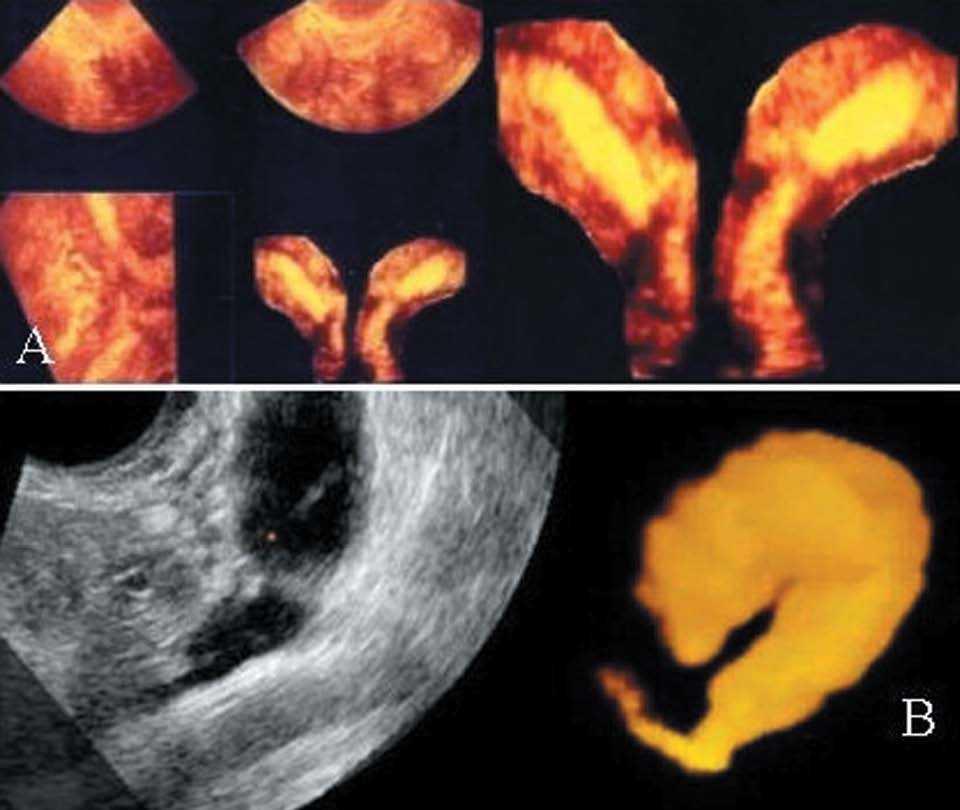

8. Corte mágico (Magic Cut, tijera o escalpelo electrónico). Permite realizar cortes tridimensionales dentro de la imagen adquirida, eliminando el área no deseada y dejando sólo la estructura que desea mostrarse (figs. 4A y 5A).

Figura 4.A) Útero didelfo. Presentación multiplanar (izquierda) y la imagen de la cavidad endometrial extraída del útero (derecha y corte mágico). Nótese que el tabique es largo y se extiende hacia abajo separando 2 cuellos independientes. El contorno exterior del fondo uterino está mostrado en el plano coronal de forma lisa, que indica un tabique o separación, no un septo y no es un útero bicorne. B) Vista en modo inverso de un hidrosalpinx; nótese, además, el uso de la herramienta Magic Cut que deja la trompa aislada con el hidrosalpinx. (Cedido gentilmente por I.E. Timor-Tritsch15.)

10. Modo Inverso. Visualiza estructuras hipoecoicas complejas, incluida la información del flujo vascular. El modo inverso consiste en un software que invierte las estructuras llenas de fluido, anecoicas, a vóxeles ecoicos, de esta manera desaparece la estroma y se muestra nítidamente la estructura llena de líquido estudiada (fig. 4B).

Patología tubárica

El modo inverso permite una delimitación precisa de las trompas con colecciones líquidas, como el hidrosalpinx y el piosalpinx (fig. 4B). Ha tenido especial aplicación en el estudio de todos los trastornos inflamatorios.

Patología uterina

Casi todas las enfermedades benignas y malignas pueden beneficiarse al situar de forma más exacta las lesiones, pero en especial las que precisan otras técnicas para el completo diagnóstico (histerosalpingografía, histeroscopía, etc.). Un campo de especial aplicación, donde ha supuesto un avance diagnóstico excepcional, mejor que las técnicas radiográficas, es en el estudio de la malformaciones müllerianas16 (fig. 4A).